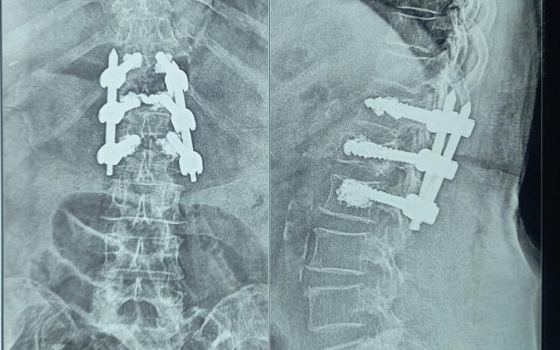

Dr. Somashekar D is an experienced spine surgeon in Bangalore. He is currently practising as a Consultant - Spine Surgery at Manipal Hospital Jayanagar, Bangalore. With nearly 10+ years of expertise in spine care, Dr. Somashekar has established himself as a highly skilled spine surgeon, contributing to over 1,500+ spine surgeries independently, ranging from simple decompressions to complex spinal reconstructions. His practice is deeply rooted in precision-based techniques and evidence-guided clinical protocols, ensuring both safety and long-term functional outcomes for his patients. He is a top spine surgeon in Jayanagar.

We offer comprehensive treatment for spine issues that is on par with any leading spine center worldwide. Our services encompass both non-surgical and surgical treatments tailored to address your specific condition. Our expertise covers a wide range of spine surgeries, including minimally invasive spine surgery, cervical spine surgery, scoliosis surgery, and complex spine surgeries.

Covers a wide range of spine surgeries, including complex spine surgeries.